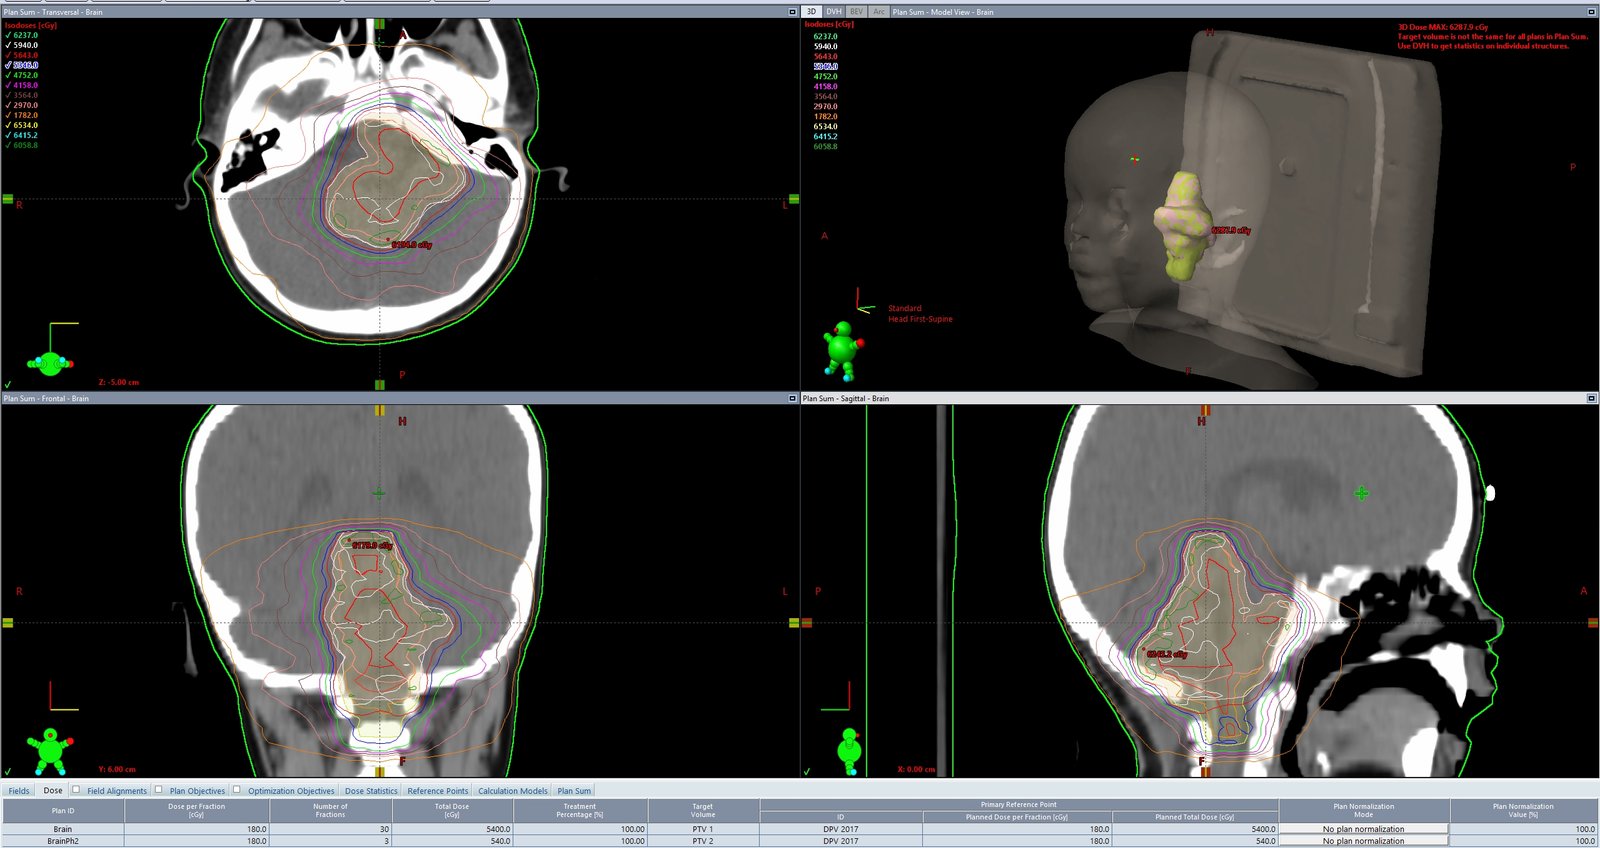

Standard of care for primary brain tumors is VMAT. In recent years, VMAT has been used for palliative radiation dosimetry as well. Stereotactic radiosurgery can deliver extremely high doses to individual brain mets with as little as only one isocenter.